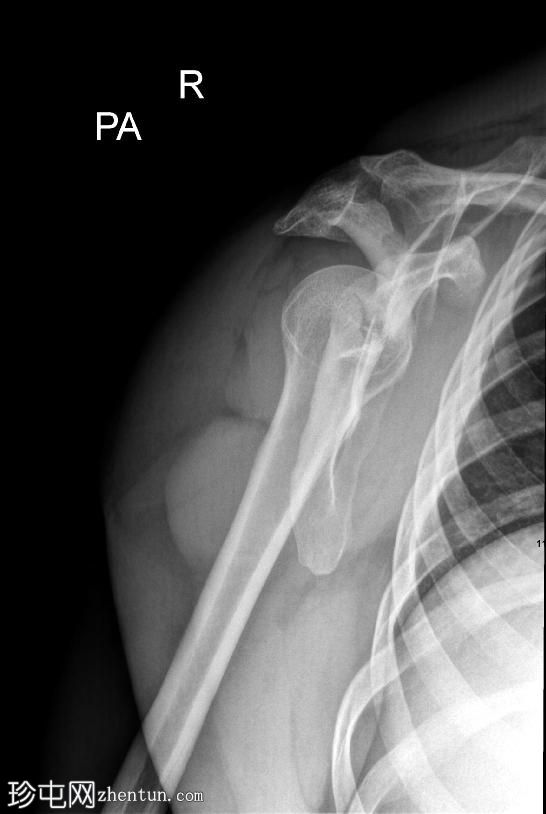

正面

右侧肩胛骨骨折,累及肩胛盂、肩胛颈和肩胛体。肱骨头与肩胛窝对位良好,提示无肩关节脱位。

肩部和肩胛骨周围有弥漫性软组织肿胀。

本例X光片显示骨折累及肩胛盂、肩胛颈和肩胛体,提示力量显著通过肩胛带传递。肩胛盂受累尤为重要,因为它可能损害盂肱关节的稳定性和关节的一致性。

肩关节无脱位且肱骨头排列完整是有利的发现。然而,由于解剖结构复杂且可能在关节内延伸,建议进行CT扫描以更好地明确骨折形态并指导手术计划。